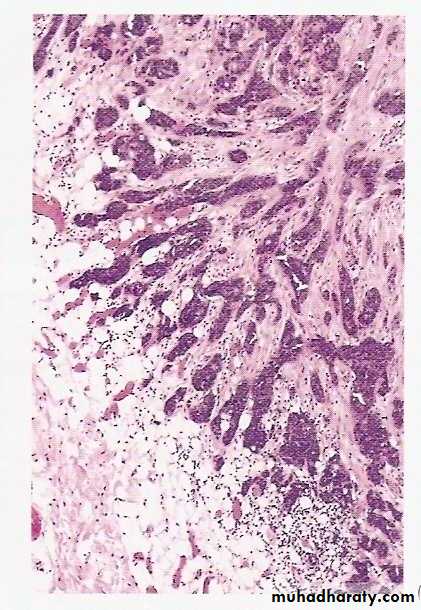

Histopathological features of anaplasia:

Cellular and nuclear pleomorphism refers to variation in size and shape of cells and their nuclei.

Hyperchromatism refers to dark staining of nuclei due to abnormally increased chromatin (nucleic acids contents), a reflection of aneuploidy.

Increased nuclear-cytoplasmic ratio (N/C) reaching nearly 1:1 (instead of the normal 1:4-6).

Abundant mitoses reflecting increased proliferative activity

Abnormal mitoses, e.g., tripolar spindles (normally mitosis is bipolar).

Tumor giant cells containing a single giant polypoid nucleus or multiple nuclei.

Prominent nucleoli

Cytoplasmic basophilia reflecting active protein synthesis.

Loss of orientation and disarray of tissue architecture (loss of polarity).

High-power detailed view of anaplastic tumor cells shows cellular and nuclear variation in size and shape. The prominent cell in the center field has an abnormal tripolar spindle.